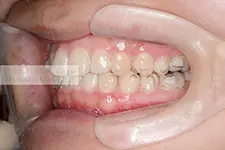

4本の先天性欠如歯と、2本の埋伏歯を有し、開窓牽引と空隙閉鎖を行うことで欠損部補綴を行わないで咬合再構成を図った空隙歯列症例

| 主訴 | 出っ歯と前歯の隙間が気になる。奥歯の隙間を閉じて欲しいが、矯正歯科治療後にブリッジ補綴やインプラント補綴などはやりたくない。矯正歯科治療だけで隙間を閉じて歯並びを仕上げてほしい。 | ||

| 年齢・性別 | 13歳未成年男性 澤村 悠里様 | 治療に用いた主な装置 | マルチブラケット |

| 抜歯部位 | 下顎左右5番 | 治療期間 | 4年 |

| 治療回数 | 69回 | 治療費 | 120万円~140万円 |

| 治療内容 | 4本の先天性欠如歯と2本の埋伏歯を有していたため重度の空隙歯列を呈していました。初診時年齢が13歳であったため、下顎骨の成長が長期に継続することが予測され、2期分離治療による矯正歯科治療を行ないました。 | ||